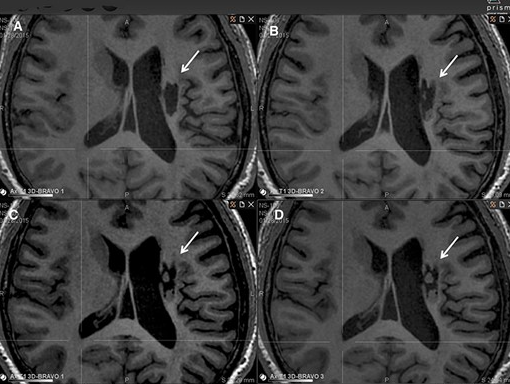

影像學檢查:在 6 個月的隨訪中,所有 9 名受試者均觀察到新組織,源自腦軟化梗塞腔。該腔內組織外觀具有以下特征:短期活力(術后第一次 MRI 與基線相比的組織外觀)—9 例中有 9 例;生長(術后至少兩次 MRI 中新組織增加)—6 例中有 6 例;穩定(術后至少兩次 MRI 中新組織沒有變化;即生長平臺期,最長為 24 個月)—6 例中有 5 例;無法獲得 24 個月后的長期活力。

(A)基線時,(B) 6 個月隨訪時,(C) 12 個月隨訪時,(D) 24 個月隨訪時。